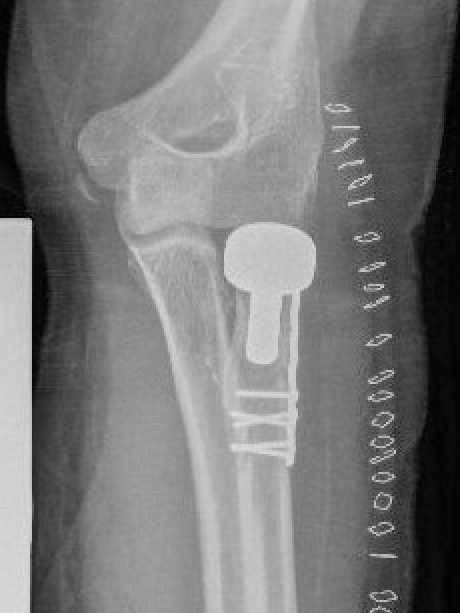

ORIF with plates

Technique

Lateral approach

- identify safe zone (90 degrees between radial styloid) and Lister's tubercle)

- lag articular surface first if required

- pre-contoured low profile plates

- distal limit is bicipital tuberosity

- check ROM intra-operatively

- plates often bulky and may limit ROM

- close annular ligament